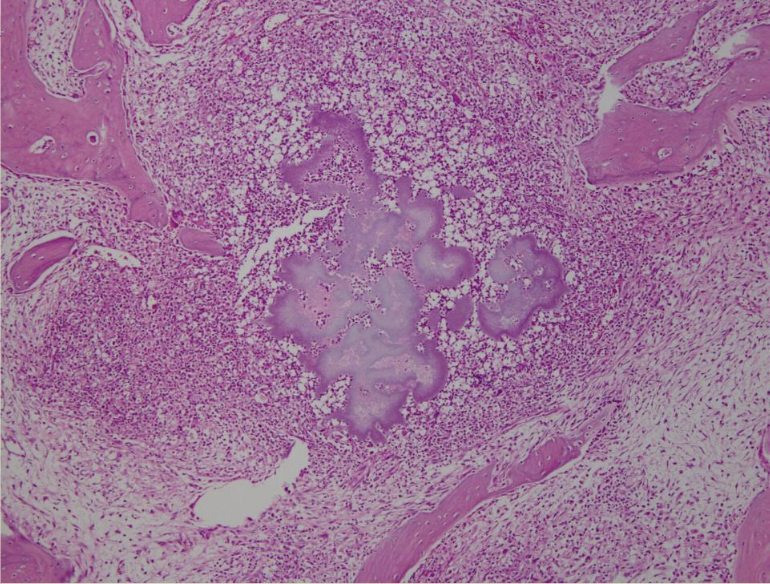

Bacterial colony in center surrounded by inflammatory cells.

Splendor Hopplie phenomena represents the Ag/Ab complex.